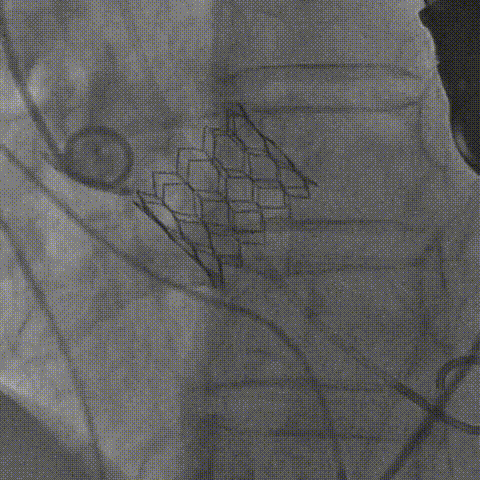

TAVI是将人工生物瓣膜通过介入导管输送到心脏主动脉瓣区打开,完成人工瓣膜的植入,恢复瓣膜功能的一种技术,具有创伤小、术后恢复快等优点。

如下图所示,取得了极其满意的效果。

瓣膜释放 瓣膜释放后造影